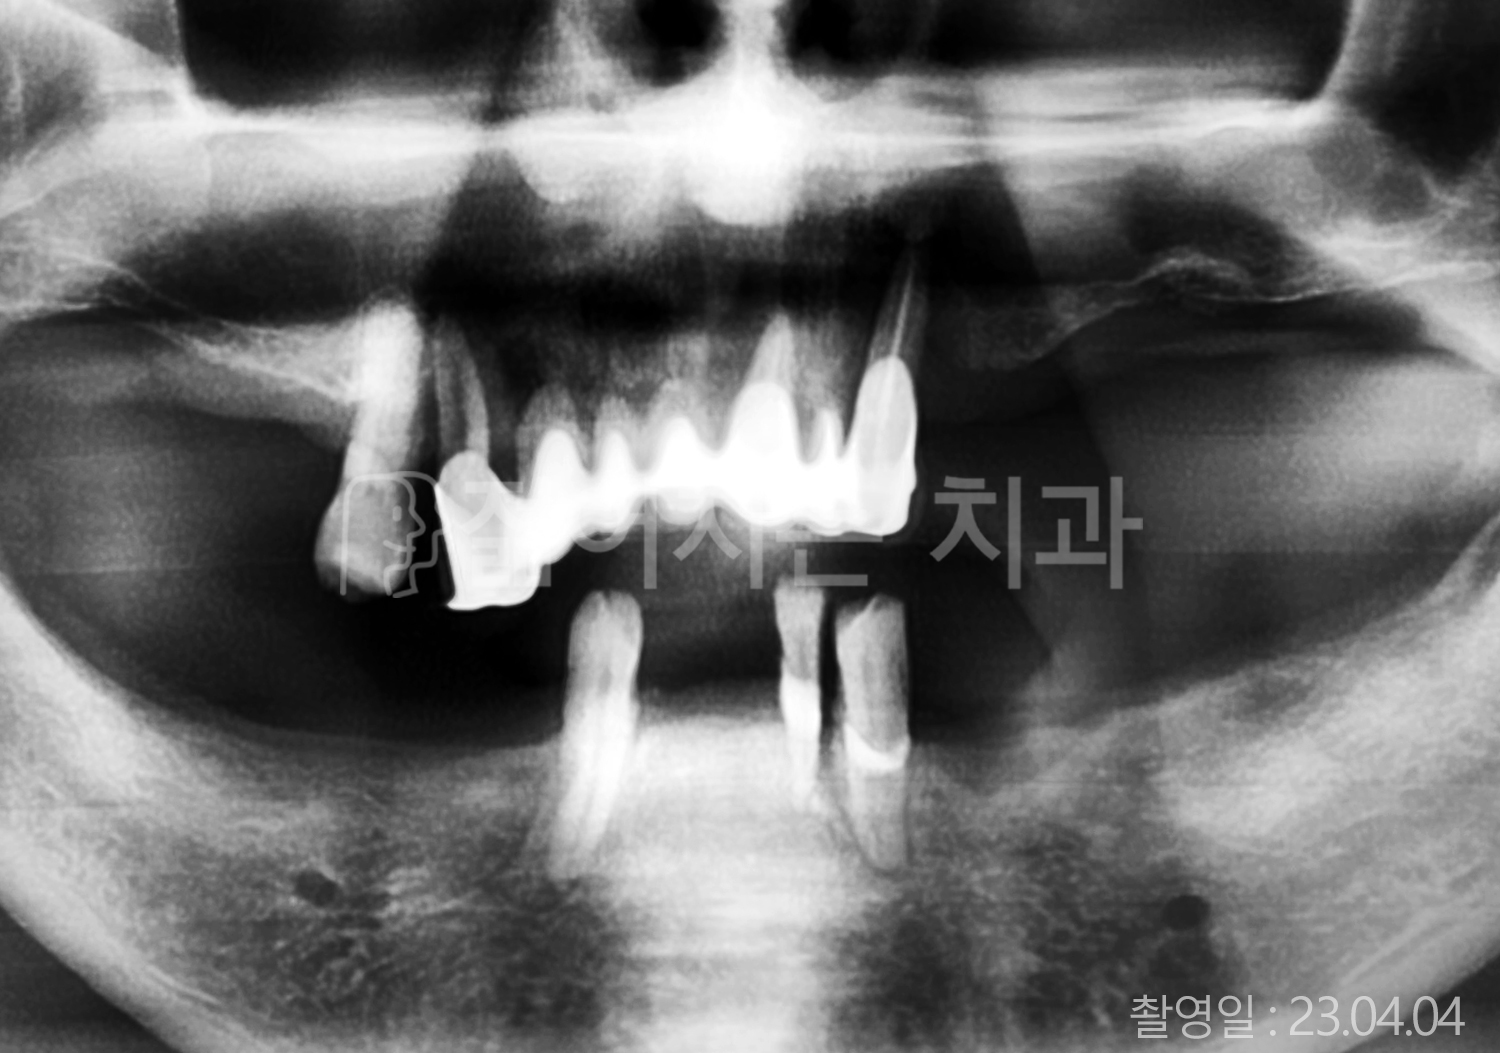

• 40대 전체치아 10개 이상 임플란트

• 50대 전체치아 10개 이상 임플란트